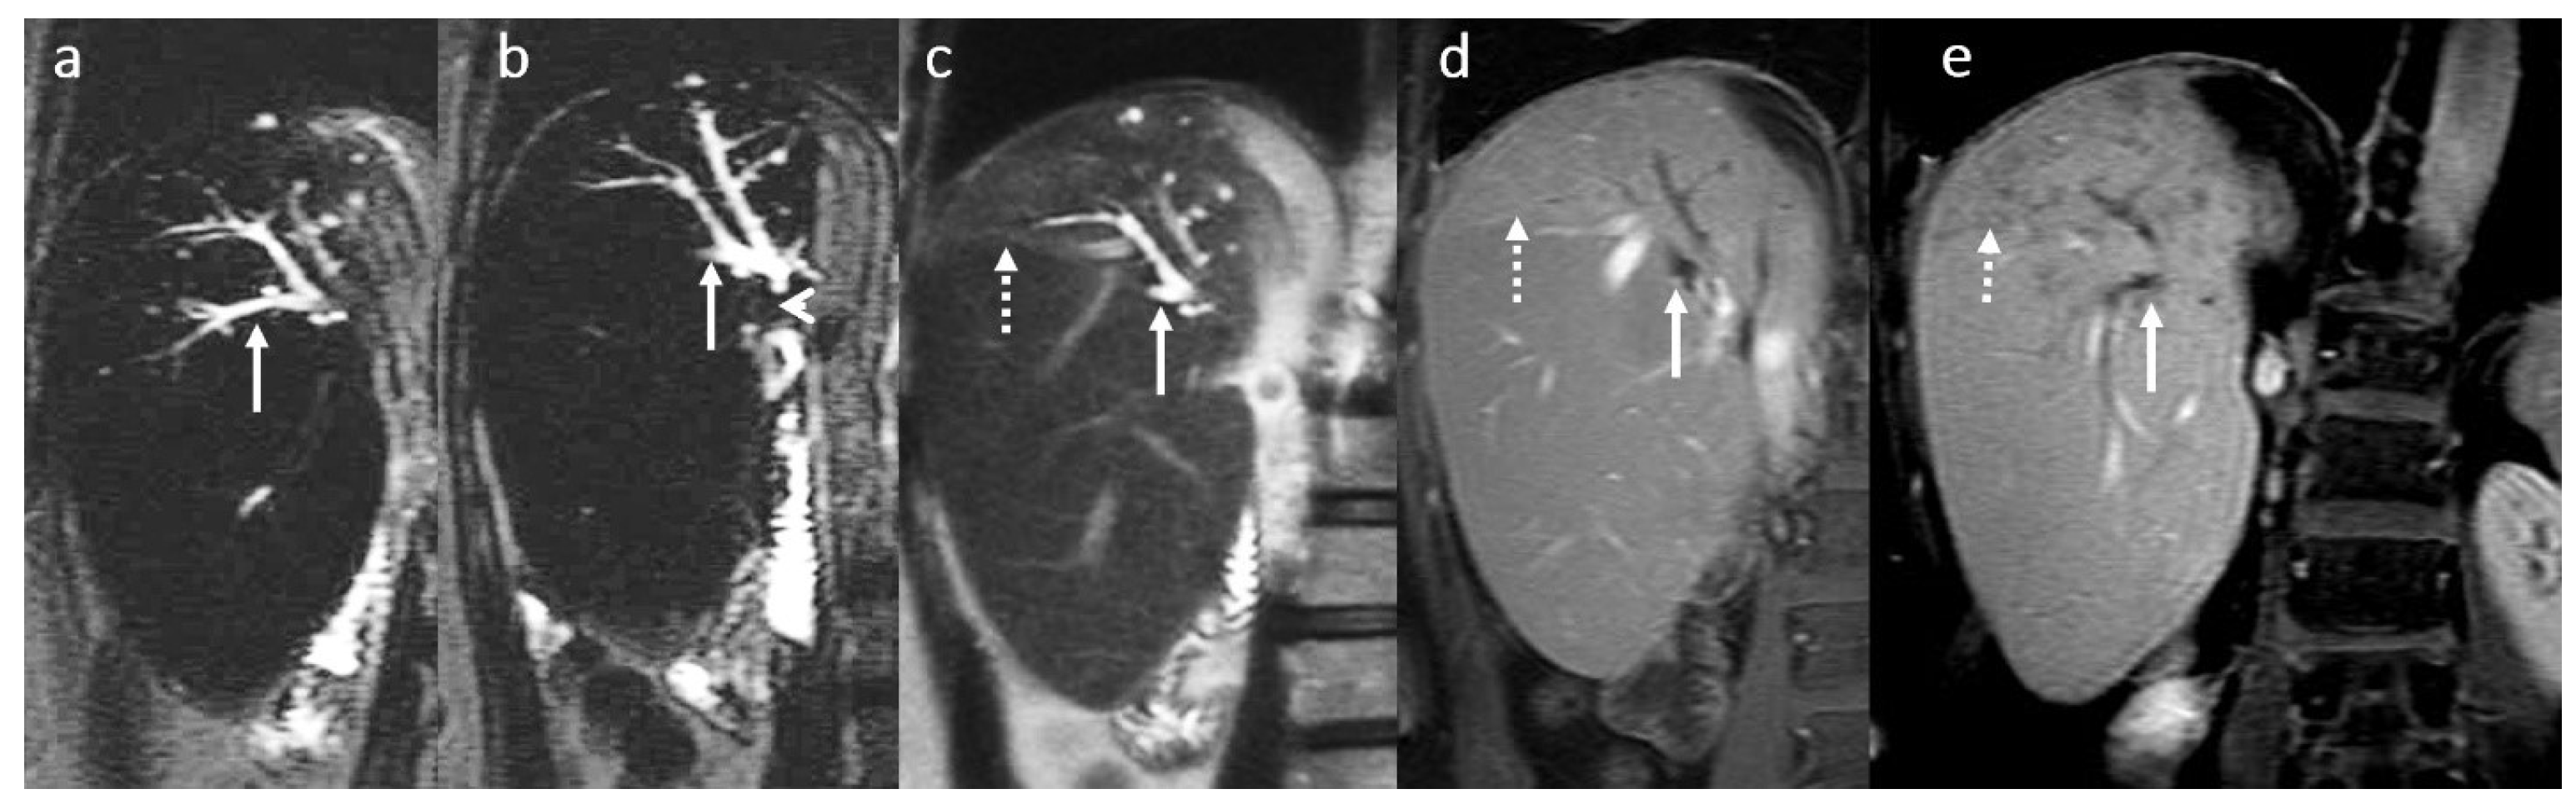

3.6. Secondary Cholangitis

3.7. BT Lithiasis